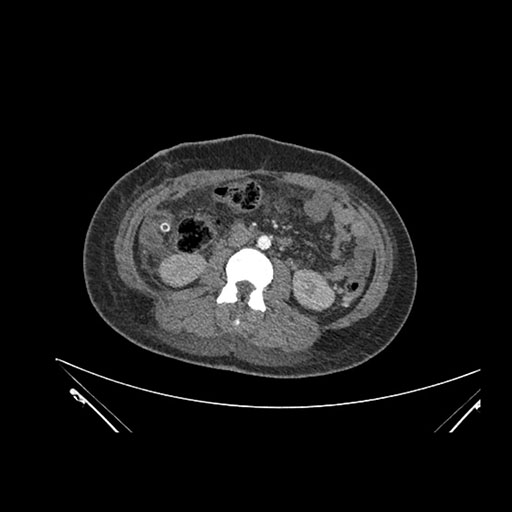

Axial Venous

Imaging analysis

Based on initial findings, which issue(s) would you be most concerned about?